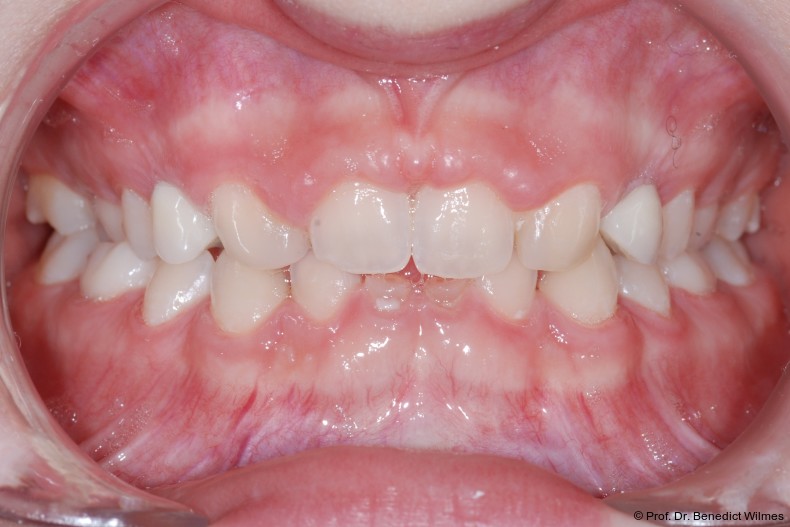

Bei einer elfjährigen Patientin fehlten bei Zustand nach Frontzahntrauma im Alter von neun Jahren beide oberen mittleren Schneidezähne (Abb. 8a+b). Als temporärer Ersatz wurden Miniimplantate (Abb. 9, 2 x 13 mm) eingesetzt und Kronen im Labor angefertigt, welche auf den Miniimplantaten verschraubt wurden (Abb. 10a+b). Die Miniimplantate wurden im Alter von 19 Jahren, also nach achtjähriger Nutzung (Abb. 11a+b), durch dentale Implantate ersetzt.

Bei einer 13-jährigen Patientin lag eine Aplasie multipler Zähne, unter anderem auch der oberen seitlichen Seitenzähne vor. Die Eckzähne brachen bei dieser Patientin direkt neben den mittleren Schneidezähnen durch (Abb. 12).

Nach Abschluss der kieferorthopädischen Pfeilerverteilung wurden zwei Miniimplantate in Regio 3er inseriert (2 x 13 mm). Nach Herstellung im Labor wurden Kronen auf den Miniimplantaten aufgeschraubt (Abb. 13+16a–d). Auch hier wurde darauf geachtet, dass die Kronen aus der Okklusion geschliffen wurden (Abb. 14). Bei den Nachkontrollen zeigten sich ebenfalls stabile Miniimplantate und ein entzündungsfreies Implantatlager ohne erkennbare Atrophie des Knochens (Abb. 15 und 16a–d).